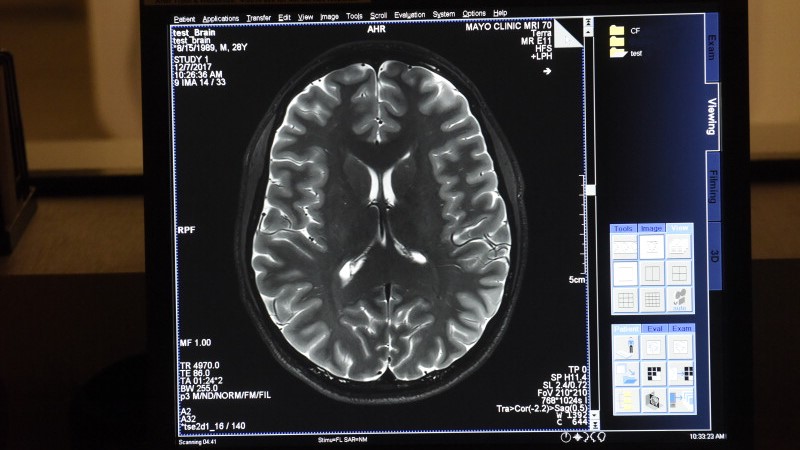

Sophisticated imaging technology that uses higher magnet strengths and computational tools allow Mayo Clinic doctors to identify where seizures originate within 1 millimeter. In the past, physicians may have been unable to identify the small lesions or abnormalities in the brain that caused their epilepsy.

Understanding the exact root cause of a seizure is critical for informing the most effective treatment plan for an individual patient. Mayo Clinic clinicians and researchers work in teams to collaborate across medical specialties to consider all of a patient’s medical needs beyond their seizures. Mayo’s subspecialized epileptologists subspecialize in the various root causes of epilepsy including genetic, structural, autoimmune or neurometabolic.

Successful treatment starts with an accurate diagnosis. Whether you are newly diagnosed or if you’ve been living for years with a neurological disorder, Mayo's locations in Arizona, Florida and Minnesota use the latest diagnostic imaging to pinpoint the exact cause of your condition.